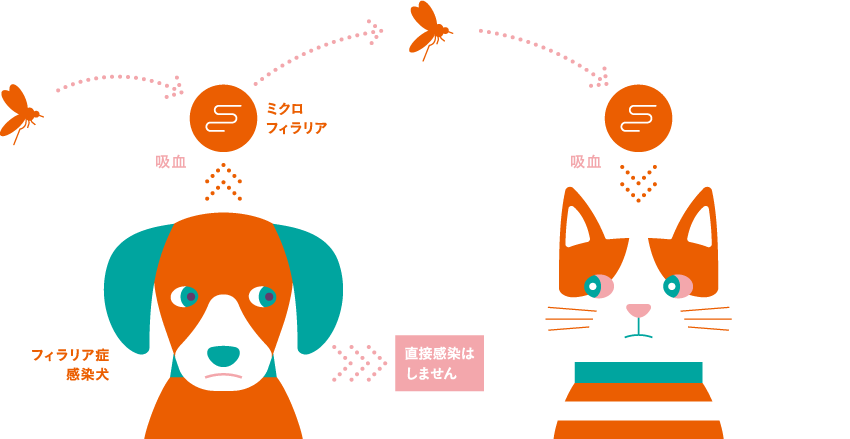

フィラリアの生態を知ろう

ねこの体内での一生

フィラリアの成長はいくつかのステージに分かれています。

予防しようどこから感染するの?

主にフィラリア感染犬の血液を吸った蚊がねこの血液を吸ったときに、フィラリアの幼虫がねこの体内に侵入し、感染します。